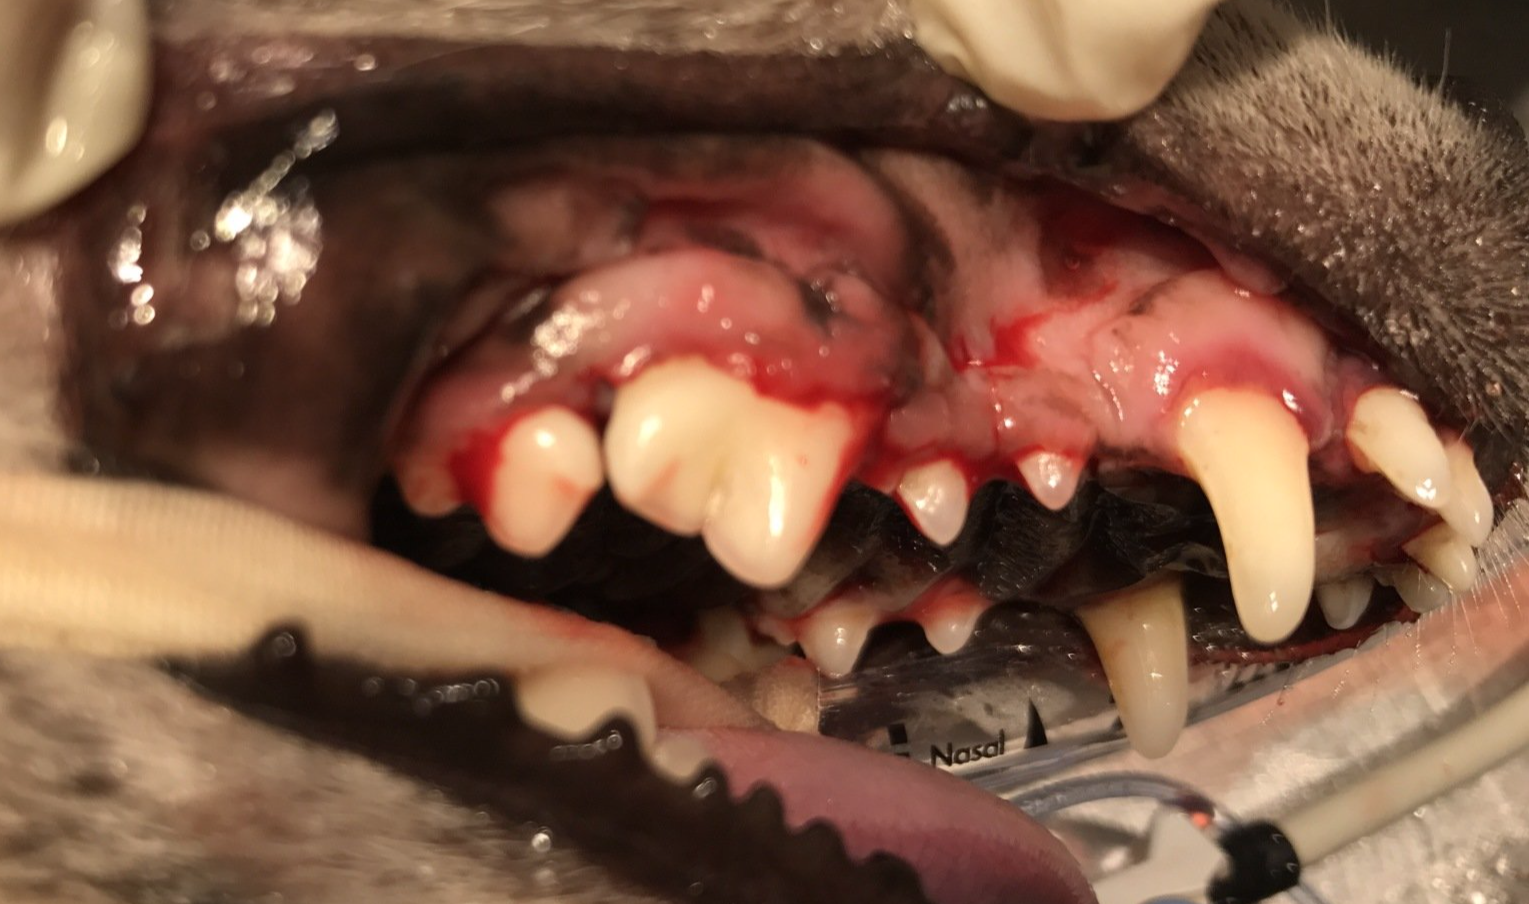

Wortelpunten verwijderen, na een niet goed uitgevoerde totale gebitsextractie, bij de kat

Op foto 1 en 3

zie je een heel erg ontstoken bekje, het tandvlees in de hele bek is vurig rood en super pijnlijk.

Op foto 2 en 4

zie je de röntgenfoto's waarop nog allemaal kleine stukjes wortel zichtbaar zijn. Door een eerdere, niet goed uitgevoerde, behandeling zorgen zij voor het blijven bestaan van de tandvleesontsteking. Zeker bij een kat met dit probleem is het super belangrijk alle elementen volledig te verwijderen!